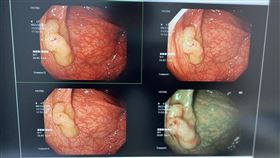

好險!早期大腸癌 內視鏡切除免開刀

大腸直腸癌是國人十大癌症之首,平均每30分鐘新增1人...